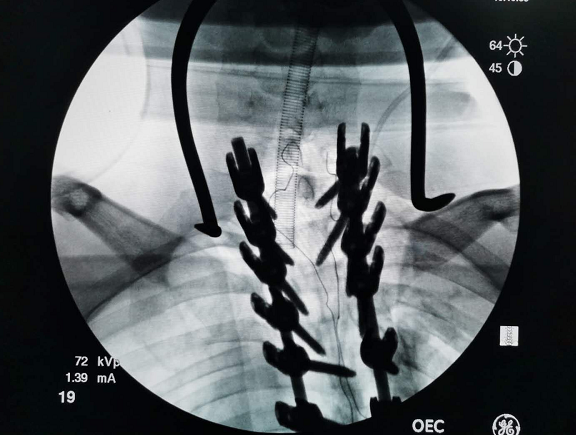

彭建兴主任医师带领医疗组进行了充分的术前准备,并进行了全院会诊。经过6个多小时的手术,张强弯曲的脊柱得以矫正恢复。彭医生说,张强的术后恢复愈合非常好,神经功能、呼吸功能都比以前顺畅多了,还可以增高4~5公分。最主要是矫型之后,脊椎不受压了,心肺功能不受影响。

彭医生表示,这次手术非常成功,不仅仅能改变张强背部的凸起,还能让张强重新拾起自信。彭医生说,现在张强最大的变化就是脸上有了笑容。他们将会为张强制定康复训练,让他回归新生活。